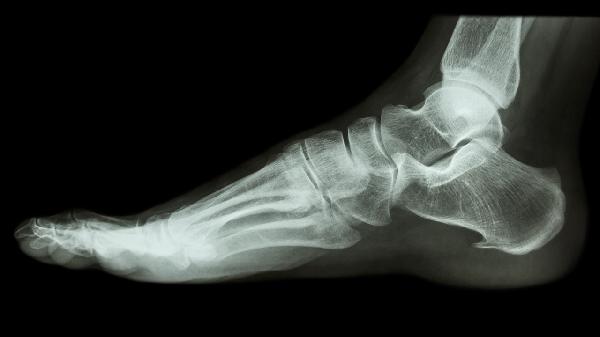

3、跌打损伤

跌打损伤包括肌肉拉伤、韧带扭伤、软组织挫伤等情况,主要表现为局部红肿、疼痛、瘀血等症状。筋骨痛消丸具有活血化瘀、消肿止痛的作用,适用于轻中度跌打损伤的治疗。用药期间应注意患处制动休息,严重损伤需就医检查。类似药物还有三七伤药片、云南白药胶囊等。